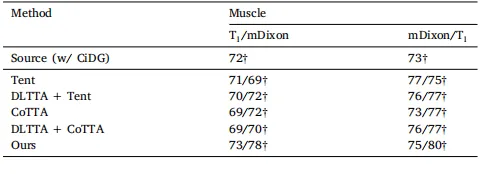

We evaluated our method and other benchmarking methods onfive datasets of different types of medical images. Each dataset has aunique distribution due to images collected from multiple sites and/ormodalities. We describe each dataset in paragraphs below.The first dataset is a cross-site binary prostate segmentation datasetfrom T2 -weighted MRI scans collected from six different sites where12–30 scans were available for each site (Bloch et al., 2015; Lemaîtreet al., 2015; Litjens et al., 2014).The second dataset is a cross-site and cross-modality multi-class(liver, left and right kidneys, and spleen) abdominal segmentationdataset between 30 CT and 20 MRI T2 -SPIR scans (Landman et al.,2015; Kavur et al., 2021).The third dataset is a same-site cross-modality muscle segmentationdataset with 13 lower-leg muscles and bones between 30 MRI T1 andmDixon scans (Zhu et al., 2021).The fourth dataset is a cross-site and cross-modality whole braintumor segmentation dataset (Menze et al., 2015) from over 100 MRI T2FLAIR and T2 -weighted scans. The dataset was collected by two centers.The last dataset is a cross-site and cross-modality heart segmentation dataset of four substructures (left ventricle, myocardium, leftatrium, and ascending aorta) from 20 MRI balanced steady-state freeprecession (b-SSFP) and CT scans (Wu and Zhuang, 2020).All scans were normalized to zero mean and unit variance beforebeing reformatted to 2D. Following other studies (Ouyang et al., 2023;Zhu et al., 2022; Wu and Zhuang, 2020), the prostate, brain tumor,and abdominal scans were resized to 192 × 192 pixels while the heartsubstructure and the muscle scans were center-cropped to 256 × 256and resized to 128 × 128 pixels, respectively. Lastly, a window of[−275, 125] in Houndsfield units was applied to CT scans and the top0.5% of the histogram of MRI scans was clipped.For the first dataset, we treated each site as the source domainand adapted to all other sites. The adaptation was performed in bothalphabetic and randomized orders. For example, the source model wasfirst trained on site A, then adapted to sites B, C, D, E, and F (alphabetic)and also adapted to sites F, E, D, B, and C (randomized). For otherdatasets, we first performed adaptation from modality A to B, then fromB to A. All experiments were performed in an online and continuoumanner: each test scan arrived randomly and was broken down intomultiple batches if needed. The model adapted itself to each batchbefore making a prediction. U-Net with an EfficientNet-b2 backbonewas used as the source model for all our experiments. We trained thesource model with ERM to provide a baseline model susceptible todomain shifts, and also with CiDG to produce another baseline thatis domain-generalized (i.e., resilient to domain shifts). Both baselinemodels were used by all the benchmarked adaptation methods toevaluate their efficacy in improving a baseline model’s target-domainperformance in various conditions. The Adam optimizer (Kingma andBa, 2015) was used with a learning rate of 0.001 and a batch sizeof 32. 𝛼 was set to 0.5 to achieve a balance between the local andglobal cross-task consistency terms, and 𝛽 was set to 1 to fully utilizethe self-regularization of the student model. 𝜅 was set to −1500 toapproximate the inverse transformation from the segmentation labelsto SDF maps, and 𝑝 to 0.01 to restore roughly 1% of model parametersback to their initial state with each gradient update. The model wasupdated for two steps (i.e., two gradient updates per test batch) forthe muscle, heart substructure, and brain tumor segmentation, fivesteps for the prostate segmentation, and ten steps for the abdominalsegmentation. The number of patches 𝑀 is determined by the slidingwindow size and its stride, which were empirically set to 48 and 32,respectively. 𝑁 was set to 12of 𝑀 to select the top 50% of patches withthe highest uncertainty scores to enforce effective local cross-task regularization while maintaining a reasonable computational efficiency.All hyperparameters except for the number of gradient update stepsare shared across all datasets. Our methods were implemented usingPyTorch 1.10.0 and trained on one Nvidia Tesla V100 GPU.2In addition, we calculated the final performance of each modelby using each model to re-predict the segmentation labels of all testsamples after the adaptation was completed. We then compared thefinal performance of each model against their running performanceto evaluate their ability for continual adaptation. Here, the term ‘running performance’ represents the cumulative evaluation metric scorescalculated from results produced by the model after each test batchwhile the adaptation was ongoing. On the other hand, the ‘final performance’ refers to the scores calculated from the results produced by the‘adapted’ model in one go after the adaptation had been completed. Theperformance was quantitatively evaluated by their volume-wise DiceSimilarity Coefficient (Dice, in %, the higher the better) and AverageSymmetric Surface Distance (ASSD, in mm, the lower the better).The statistical significance between results was determined with theWilcoxon signed-rank test at the pixel level. The significance thresholdwas set to 0.05.Lastly, we performed the adaptation at both the domain level(i.e., continuous adaptation) and single-image level to highlight thevalue of continuous adaptation. When performing the adaptation at thesingle-image level, the model was adapted to each test batch beforere-initializing its weights for the next test batch, whereas the model’sweights were continuously updated throughout the adaptation processfor the domain-level adaptation.

第三个数据集:这是一个同站点的跨模态肌肉分割数据集,包含小腿的13块肌肉和骨骼,数据来源为30个MRI T1和mDixon扫描(Zhu等,2021)。

Table 1 Comparison on four datasets. denotes the results obtained by reproduced based on the publicly codes. The best and second-best results are marked in bold and underlined, respectively

表 1 四个数据集上的比较。表示基于公开代码复现所得的结果。最佳结果和次优结果分别用加粗和下划线标注。